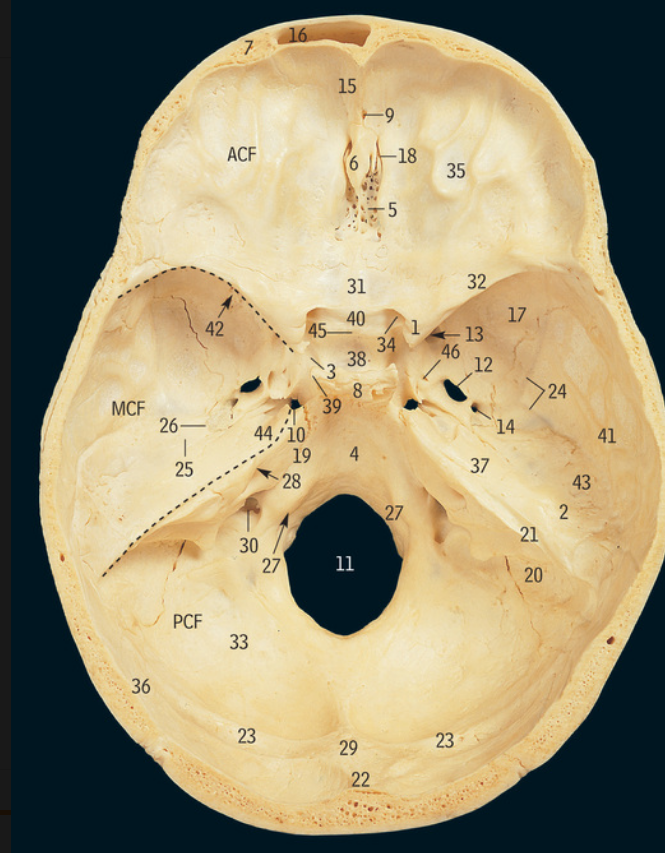

5

Cribiform plate

6

Crista galli

17

Greater wing of sphenoid bone

32

Lesser wing of sphenoid bone

38

Pituitary fossa

34

Optic canal

42

Superior orbital fissure

12

Foramen ovale

13

Foramen rotundum

14

Foramen spinosum

27

Hypoglossal canal

11

Foramen magnum